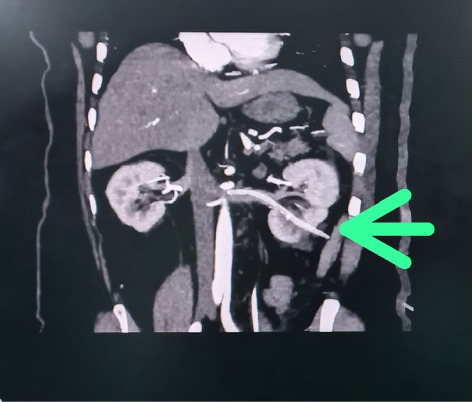

Background: After percutaneous nephrolithotomy (PCNL), intravenous misplacement of a nephrostomy tube is a very rare clinical occurrence. This report summarizes the characteristics and management of intravenous misplacement of a nephrostomy tube. Case Presentation: We present a rare case of intravenous nephrostomy catheter misplacement after PCNL in a 63 years old male. The tip of the tube was located in the left renal vein. The patient was managed conservatively and treated safely. Conclusion: Intravenous nephrostomy tube misplacement is a rare PCNL complication. Good Imaging can rule out through and through renal vein perforation and thus patients can be safely managed using conservative approach.

Abstract Image